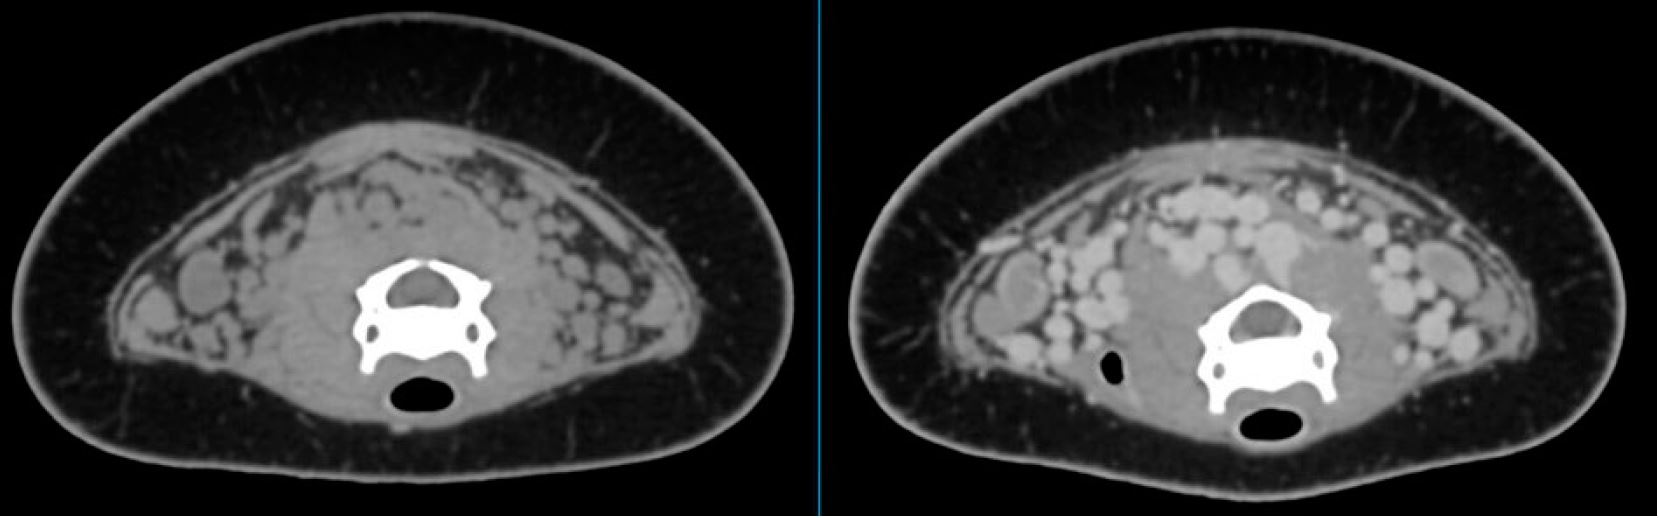

Шийний венозний синус

Постконтрастне дослідження Вінсента показало ефектне венозне сплетення в шийному відділі (мал. 8). Ці судини вбудовані в коричневу жирову тканину5. Кровотік через сплетення посилюється під час пірнання. Його точна функція невідома, але було припущено, що сплетення допомагає знизити температуру тіла, можливо, уповільнюючи метаболізм і зберігаючи кисень6.

Малюнок 8: Аксіальні зображення шиї Вінсента до і після контрастування показують венозне сплетення.